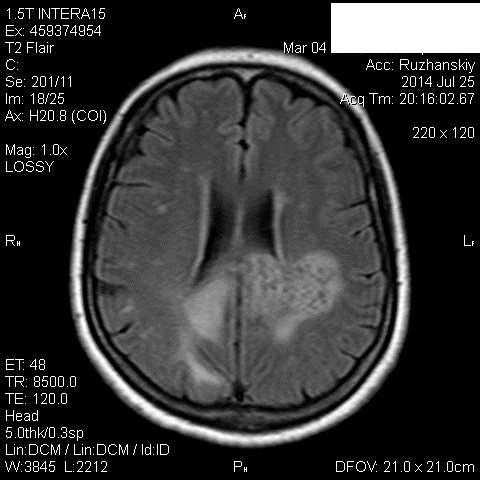

Мама приятельницы.Нарушение походки в течение 2-3 месяцев.

DDs: рассеянный склероз, токсоплазмоз, mts.

Рассеянный склероз вряд ли. Я бы добавила лимфому и глиобластому.

Думается больше о глиобластоме в форме бабочки. Из книги "Диагностическая нейрорадиология". Корниенко, Пронин.

На РС точно не похоже. Токсоплазмоз - навряд ли, т.к. "мама приятельницы", а это чаще всего бывает у ВИЧ-инфицированных.

+1 к глиобластоме.

Сегодня узнала: нейрохирурги за лимфому.Сделали КТ и подтвердили .

Сейчас  уточняют план лечения.